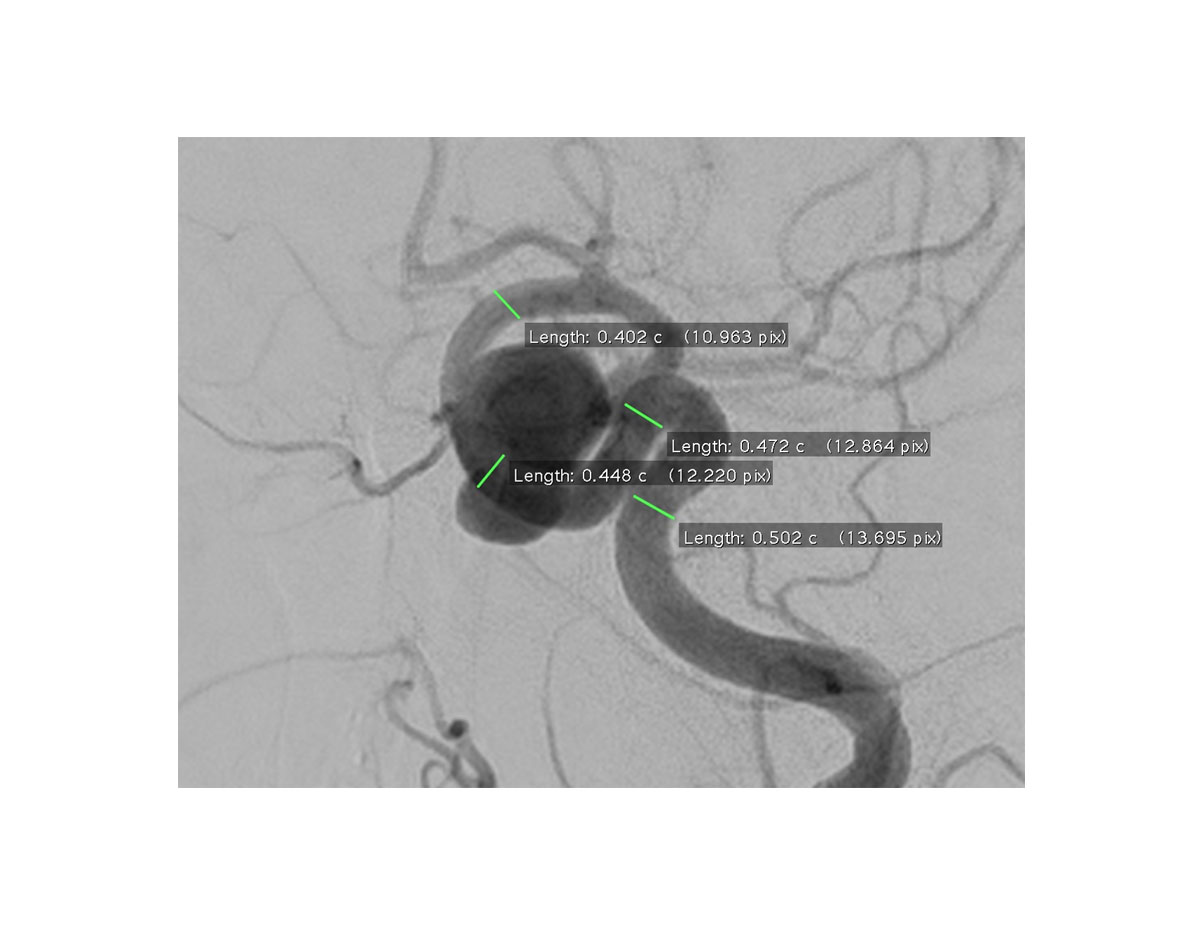

DSA, CTA, MRA等で撮影した脳血管の3次元画像データ(DICOM)から脳動脈瘤とそれに付随する脳血管を実寸大モデルで作成します。脳動脈瘤のサイズや形状、発生個所を文字通り“手に取って”把握することができます。コイル塞栓術を行う際のマイクロカテーテルのシェイピングにも有効に利用することが可能です。

DSA, CTA, MRA等で撮影した脳動脈瘤の画像をもとにモデルを作成します。DICOMと呼ばれる形式で保存されいる脳動脈瘤をスライス状に撮影した医療用画像専用ソフトウェアを用いて3次元に再構成します。不要な血管やノイズ等を除去し、データ変換を行うことで脳動脈瘤のSTLデータを作成します。このSTLデータをもとに3Dプリンターで脳動脈瘤モデルの造形を行います。

脳動脈瘤内にコイルを挿入するコイル塞栓術ではカテーテルの位置が重要になります。例えば、左図のような脳動脈瘤では、カテーテルを血管壁に一度接触させ、カテーテルの先端を脳動脈瘤の中心部分に来るようにします。このようにすることで、カテーテルが安定して設置され、コイル挿入時にカテーテルが跳ね返って脳動脈瘤の外側へと飛び出すようなことが起きにくくなります。

カテーテルの位置がしっかりと定まっているとコイル塞栓術を効率よく行うことが出来ます(コイルを無理なく沢山詰めることが可能となります)。このような効率的なコイル塞栓術を行うためにマイクロカテーテルのシェイピングが行われます。シェイピングとは文字通り、カテーテルに“形付け”を行うことで、下記図に示すような手順で行われます。

従来のコイル塞栓術ではマイクロカテーテルのシェイピングをモニター等に映した画像をもとにして行っていました。しかしながら、これでは脳血管の奥行きや実際のサイズ感を把握することが困難であり、上手くシェイピングを行うためには、ベテラン医師による熟練の技術が必要とされてきました。

脳動脈瘤とそれに付随する脳血管を、最新式3Dプリンターを用いて印刷することにより、実寸大の実形状に合わせたシェイピングを行うことが可能となります。これまで熟練の技術が必要とされてきたマイクロカテーテルのシェイピングを、誰もがよりスピーディかつ正確に行えるようになります。また、脳動脈瘤を有している患者様にとっても、自分の目では見えない部分にどのようなものが出来ているのかを“手に取って”把握することが可能になります。

2016年には3Dプリンターを使用したマイクロカテーテルのシェイピングの有用性に関して英学術論文に報告がなされています。(Ishibashi T, et al., “Tailor-made shaping of microcatheters using three-dimensional printed vessel models for endovascular coil embolization.”, Comput Biol Med, 2016 Oct 1; 77:59-63.)